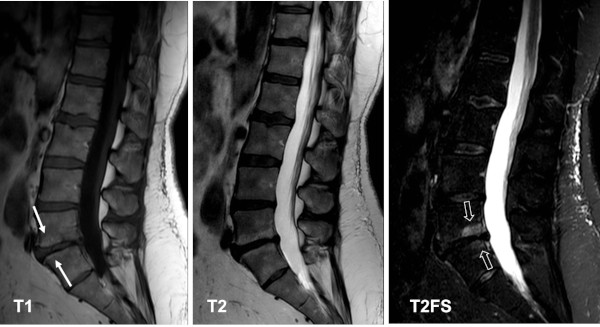

MRI of the lumbar spine, sagittal T1, T2 and T2FS image, in a middle-aged person with low back pain. There is generally reduced water content corresponding to the lumbar disks and at the lowest intervertebral space an accompanying mixture of Modic type 1 and type 2 changes. A clear delineation of the two types is best obtained by a combination of the T1 image, showing the fat deposition anteriorly (arrows), and the STIR image showing the subchondral edema posteriorly (open arrows).